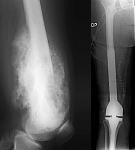

• Tumor surgery of the musculoskeletal system

• Resection of benign and malignant tumors of the bone and soft tissue

• Tumor total endoprosthesis (TEP) of all large joints and bones